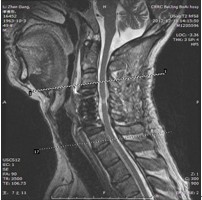

患者,男性,49岁,主因“行走不稳2个月伴右前臂麻木1个月”入院

2月前开始出现双下肢行走不稳,有踩棉花感,行走距离受限。1月前出现右侧前臂及手指麻木感。3周前诊断为“颈椎病”,保守治疗无改善,行走不稳症状加重

查体:右侧中指轻触觉、针刺觉减退,左侧上肢及双下肢感觉正常。

肌力:指屈肌群 左/右=5/4级,小指外展肌 左/右=5/4级。双侧膝腱反射亢进。双侧hoffman征阳性。肛门深感觉、自主肛门括约肌收缩存在。